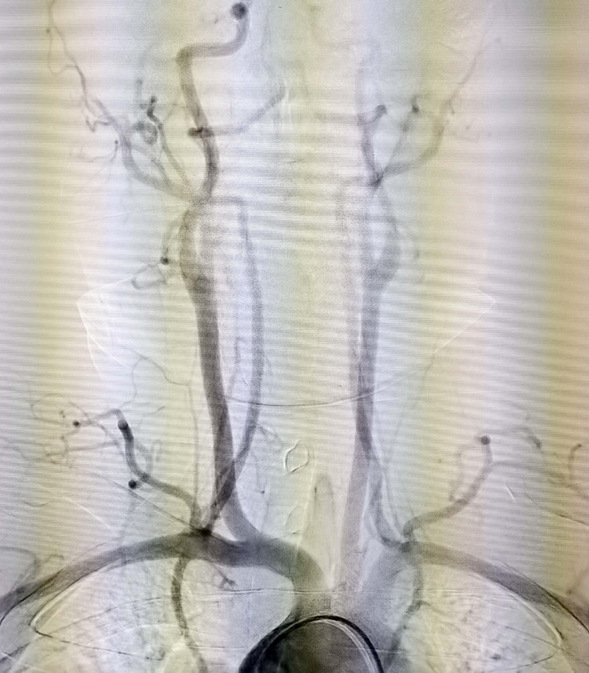

该患者男,24岁,体重95公斤,2020年4月患脑梗死病史,经过我院神经内五科治疗未留后遗症。此次患者于2022年5月22日中午12:00出现言语笨拙、右侧肢体无力,右上肢抬起费力,右下肢拖曳,约1分钟缓解,14:00再次出现上述症状,约2分钟缓解,17:00左右再次出现上述症状言语笨拙,右侧上下肢完全不能动,家长电话联系神经内五科主任迟景宏,指示急诊查头部CT及核酸,头部ct未见责任病灶,神经内五科王晓红医生及迟景宏主任查看患者:通过患者病史及入院时患者言语笨拙,右上肢肌力0级,右下肢肌力0-1级,考虑大脑中动脉栓塞,病情危重,迟景宏主任指出患者发病时间小于4.5小时可行溶栓并建议桥接取栓,于18点30分给予阿替普酶溶栓,同时请介入科评估桥接取栓,10分钟后介入科医生查看患者后,建议行脑血管造影检查必要时介入取栓治疗。患者家属同意行脑血管造影检查,王晓红医生迅给患者办理相关手续,并于18点40分前往导管室。19点55分造影结束,术中造影见左侧大脑中动脉M1段闭塞。

介入科主任刘琳与副主任莫庆国与患者家属交代病情,患者家属同意急诊取栓治疗,经商议后决定行BADDASS治疗,三件套组合:BGC+中间导管+长取栓支架,交换8F动脉鞘,引入BGC:8F×95cm;颅内支持导管:5F*125cm;取栓支架:4mm*30mm至远端病变血管,透视下释放取栓支架至病变血栓处,停留8分钟后取出大量血栓,取栓成功。复查造影见左侧经内动脉、左侧大脑前动脉、左侧大脑中动脉显影正常,血流改善,各分支显影良好,M1段未见明显狭窄,术中复查C臂CT未见颅内出血。术后患者意识清楚,问话对答切题。